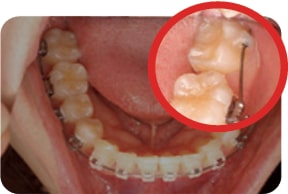

Case 1

2017. 07. 28

2017. 12. 05

2018. 03. 20

2018. 04. 28